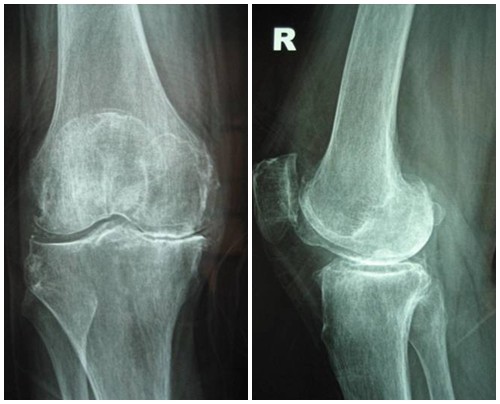

Để phân biệt các giai đoạn của bệnh thoái hóa khớp gối, cần dựa vào phim X- quang theo tiêu chuẩn chẩn đoán thoái hoá khớp của Kellgren và Lawrence như sau:

Hình ảnh của khớp gối trên phim X-quang: Khe khớp hẹp rõ, nhiều gai xương kích thước vừa, đặc xương dưới sụn, đầu xương có thể bị biến dạng.

Hình ảnh của khớp gối trên phim X-quang: Khe khớp hẹp nhiều, gai xương có kích thước lớn, đặc xương dưới sụn, đầu xương biến dạng rõ.